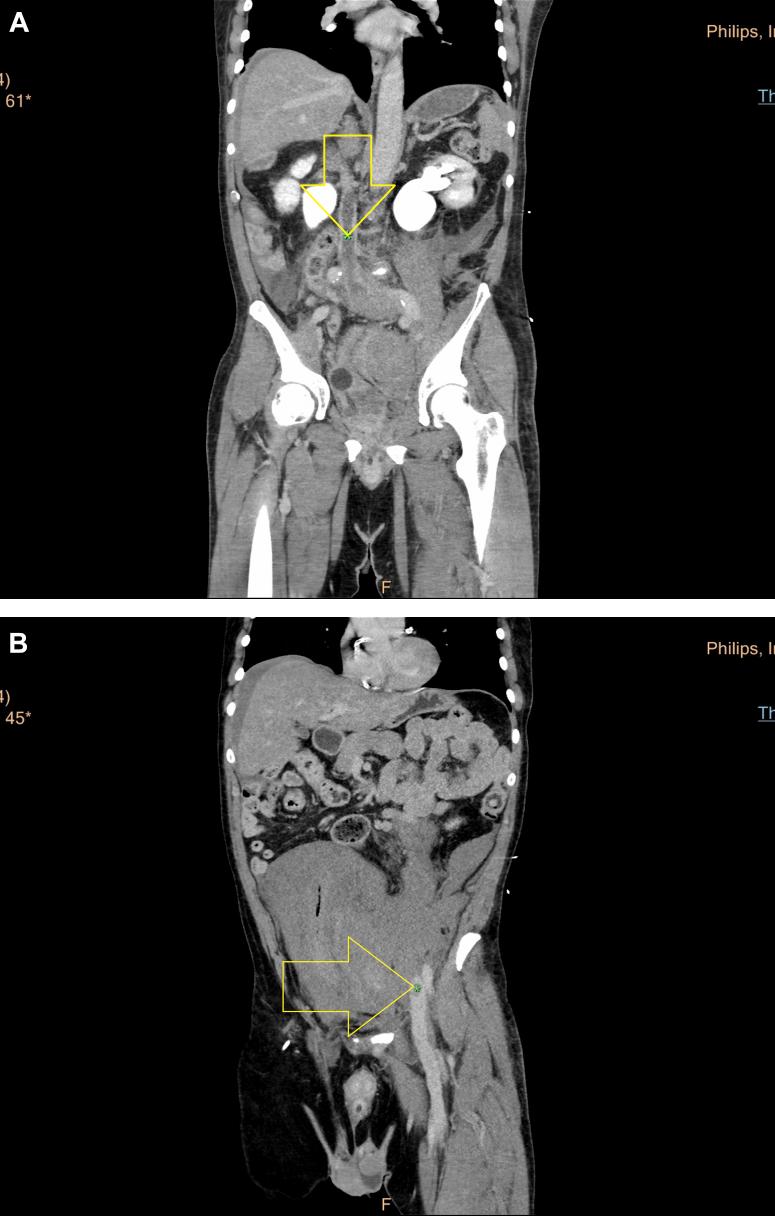

Spontaneous rupture of the iliac veins is a distinctly uncommon problem often misdiagnosed as an arterial rupture because of significant retroperitoneal bleeding. It often occurs with acute left-sided deep vein thrombosis and physical activities that exacerbate acute venous hypertension. A significant number of these patients will have anatomy associated with May-Thurner syndrome. Delayed imaging on computed tomography scanning might suggest a venous etiology for a retroperitoneal hematoma rather than arterial bleeding. We found 53 previously reported cases of iliac vein rupture Our report details two additional cases and the treatment options and outcomes.

髂静脉自发性破裂是一个明显罕见的问题,由于严重的腹膜后出血,常被误诊为动脉破裂。它常与急性左侧深静脉血栓形成以及加剧急性静脉高压的体力活动有关。相当一部分此类患者会有与May-Thurner综合征相关的解剖结构。计算机断层扫描的延迟成像可能提示腹膜后血肿的静脉病因而非动脉出血。我们发现了53例先前报道的髂静脉破裂病例。我们的报告详细介绍了另外两例病例以及治疗方案和结果。